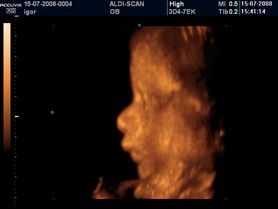

Zdjęcia płodu - twarze

Płód w 40 tygodniu ciąży (zdjęcia 3D)

Płód w 34 tygodniu ciąży (zdjęcia 3D)

Płód w 27 tygodniu ciąży (zdjęcia)

Płód w 26 tygodniu ciąży (zdjęcia 3D)

Płód w 11 tygodniu ciąży (zdjęcia 3D)